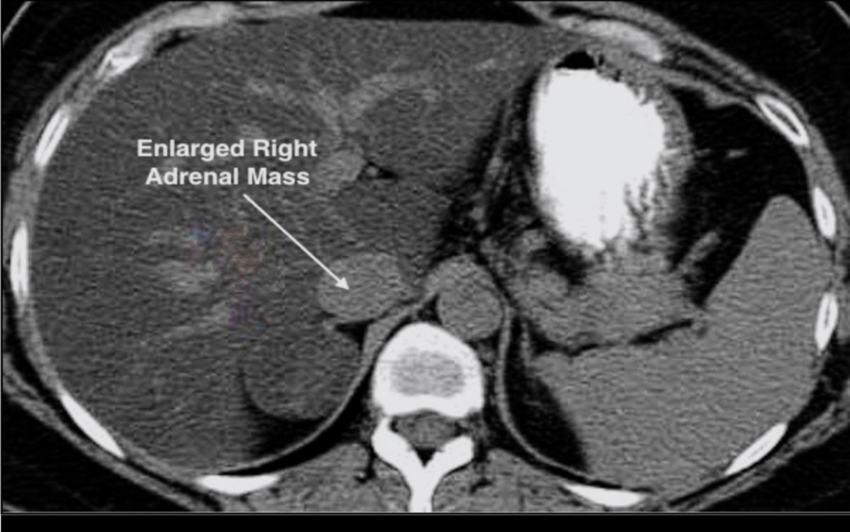

Since the early 1980’s, there has been widespread use of imaging of the chest and abdomen with CT and MRI for a variety of disorders. A very common finding is an unsuspected adrenal mass with a diameter of more than 1 cm, now referred to as an adrenal incidentaloma. The incidence increases with age, from 0.2% in childhood to 7% in old age. Once discovered, the evaluation of the mass centers on two concerns:

New techniques using CT and MRI have been very useful in separating benign from malignant adrenal tumors.

• Tumor size: Very large tumors, especially 6 cm or greater, are at high risk of being malignant.